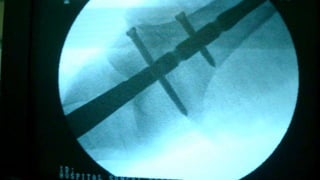

Distal Femur retrograde nailing

Brief steps of distal femoral retrograde nailing of femur